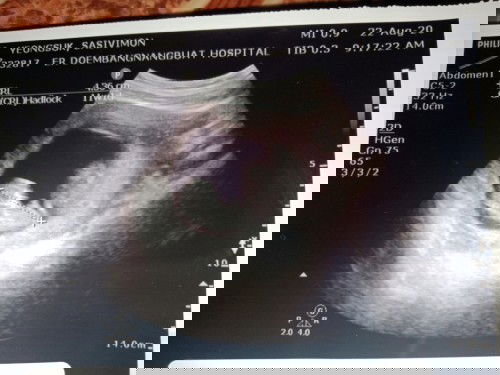

#ขอคำแนะนำหน่อยค่ะ แม่ว่า ญ รึ ช คะ พอดีหมอให้ใบซาวมา3 ใบ แต่แม่สะดุดใบนี้ หมอบอกว่าไม่มีไข่กะจู๋ หมอบอกว่าน้องนอนอ้าขาพอดี หมอบอกว่าน้องเป็น ญ แต่แม่กัวคลอดมามีไข่ อยากถามแม่ๆที่ได้ลูกสาว ว่า น้องเป็น ญ จริงไหม 20+1w #ขอบคุณล่วงหน้านะคะ